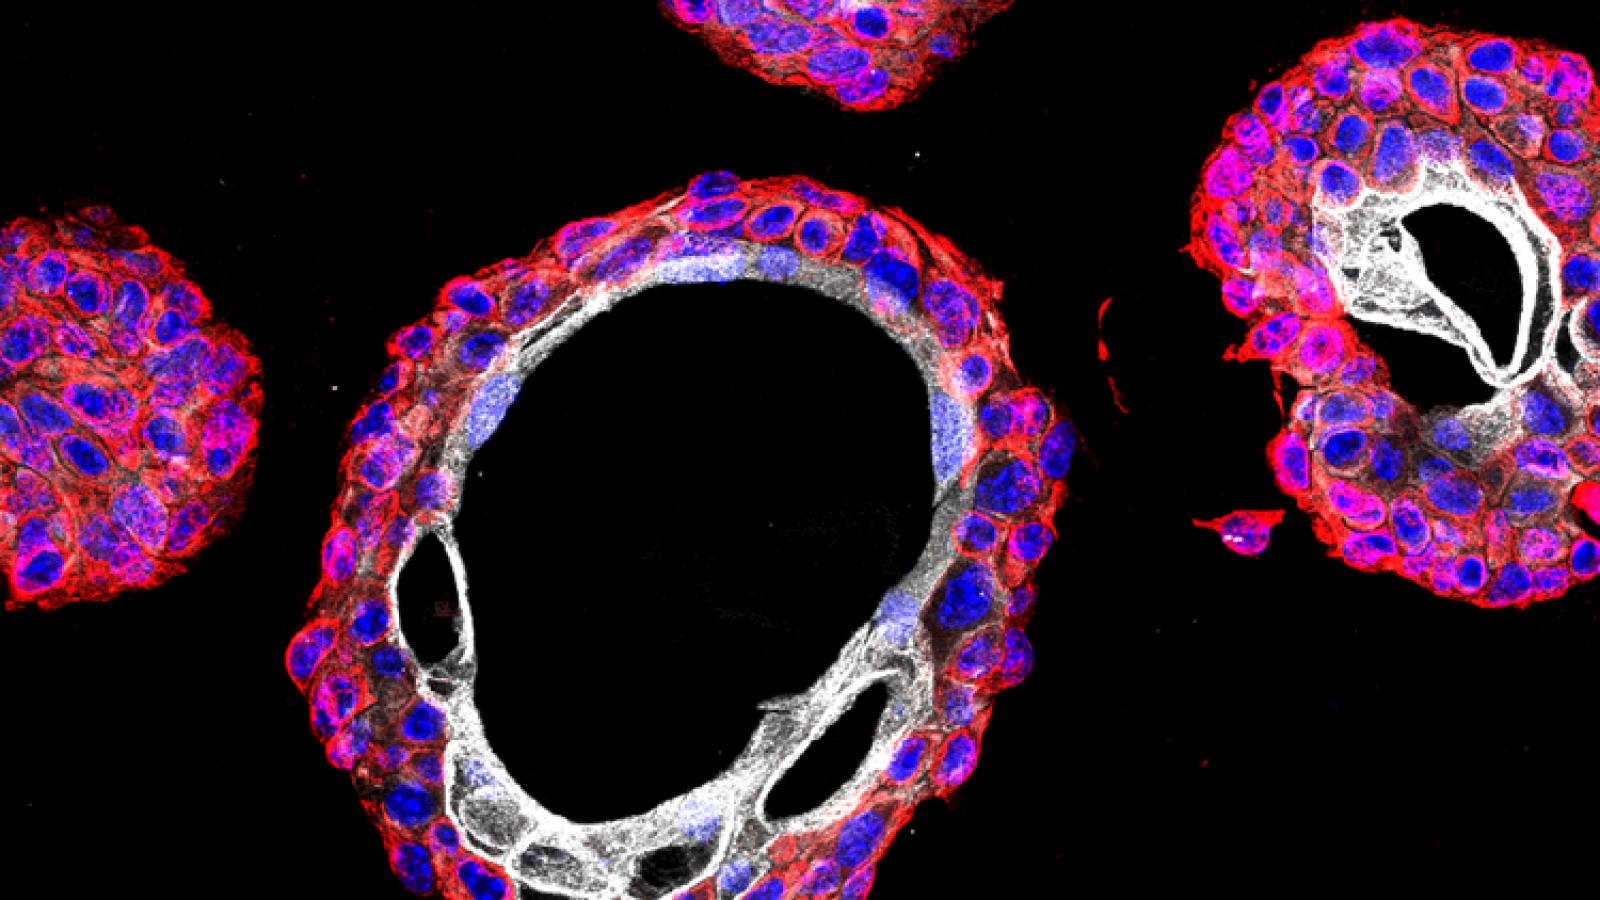

Some time ago, we described a GEMM that progresses from non-muscle invasive to muscle invasive bladder cancer, which was based on surgical delivery of an Adenovirus expressing Cre recombinase into the bladder lumen of mice with conditional floxed alleles for the Pten and Trp53 (Puzio-Kuter et al., 2009). Co-clinical analyses of chemotherapy response in this GEMM provided the rationale for an informative clinical trial for patients with high-risk non-muscle invasive bladder cancer demonstrating the relevance of this GEMM as a preclinical model of bladder cancer (DeCastro et al., 2020).

We have since developed second-generation GEMMs of bladder cancer with improved specificity of Cre-mediated recombination in bladder urothelium. Using two independent approaches to target gene recombination to specific cell types in the bladder urothelium, we found that inactivation of Pten and p53 in basal, but not non-basal, cells is sufficient for progression from NMIBC to MIBC. Cross-species analysis comparing the mouse gene signature of early bladder cancer with a corresponding human bladder cancer signature identified a prognostic signature for MIBC, supporting the relevance of these GEMMs for studying human bladder cancer and introducing a robust gene signature that may help to stratify patients at risk for developing MIBC (Park et al., 2021).